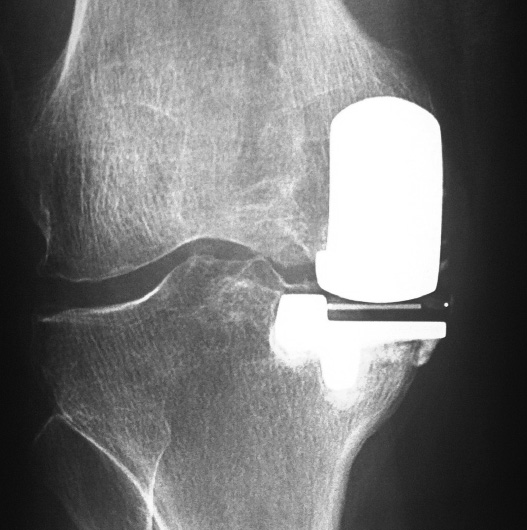

PRÓTESIS UNICOMPARTIMENTAL